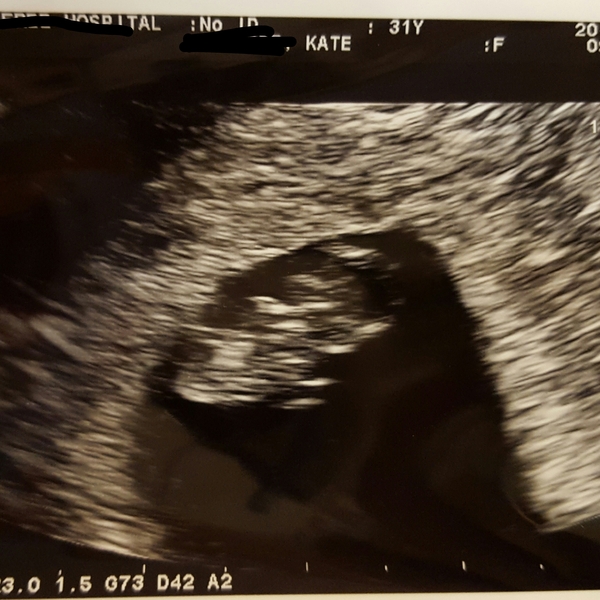

Baby is fine!!! Had my scan, and burst into tears like a crazy person when I see it in there. And then the heartbeat!! Sooo clear and strong :D she didn't tell me the numbers but I'm just happy to see he's 1) in there 2) correct size (bit bigger actually!) and 3) the heart is beating